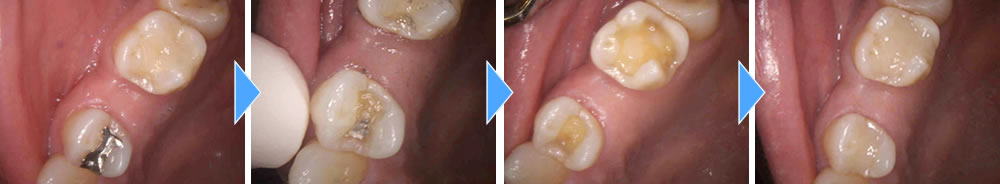

二次むし歯を治療後にハイブリッドインレーで修復した症例

年齢

20代

性別

男性

症例を見る